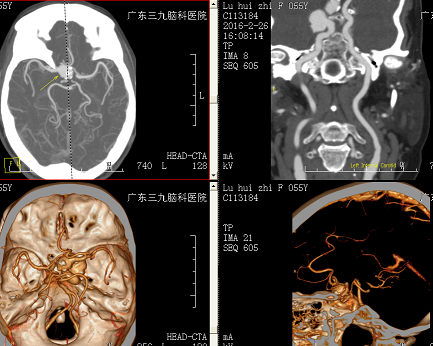

患者卢某,女性,55岁,因“间断头痛1年”入院。一年前无明显诱因出现头痛,劳累后加重,疼痛严重时口服止痛药等对症处理,入院前就诊湖南某医院,行头颅MR检查提示:右侧前床突旁异常信号结节影,CTA证实为右侧颈内动脉巨大动脉瘤。 2016-02-26就诊于我院,遂以:“颅内动脉瘤”收入院。查体:神志清楚,正确对答以及遵嘱活动,双侧瞳孔等大等圆,对光反射灵敏,四肢肌力5级,肌张力正常,生理反射存在,病理征阴性。

【诊断】:右侧颈内动脉虹吸段多发动脉瘤

【治疗】:入院实验室检查:未见明显异常。心电图示:正常心电图。腹部彩超、超声心动图提示:未见明显异常。CTA检查报告:右侧颈内动脉虹吸段示两个囊状突起,大小分别约15mm×15mm、10mm×10mm,囊壁可见斑点状高密度钙化影,邻近右侧颈内动脉呈梭形膨大。考虑:右侧颈内动脉虹吸段多发巨大动脉瘤,合并梭形动脉瘤。2016-3-6全脑血管造影显示:右侧颈内动脉虹吸段多发动脉瘤,近端动脉瘤大小约18.0mm*15.0mm,囊状,宽颈,瘤体朝右侧生长;远端动脉瘤16.0mm*12.0mm,囊状,宽颈,瘤体朝后生长。并给以栓塞治疗,栓塞后造影见动脉瘤血流改变,瘤腔造影剂滞留明显,右侧颈内动脉、右侧脉络膜前动脉显影通畅,即结束手术。术后给以营养神经、抗凝、防止脑血管痉挛等对症支持治疗。出院时患者无不适,无头晕、头痛,无恶心、呕吐,无发热,无肢体抽搐,神志清醒,对答切题,双瞳双侧瞳孔3mm,对光反射灵敏,心肺腹均未见明显异常,双侧眼球活动自如,肢体肌力5级,肌张力正常。腹股沟伤口无渗出,足背动脉搏动好。